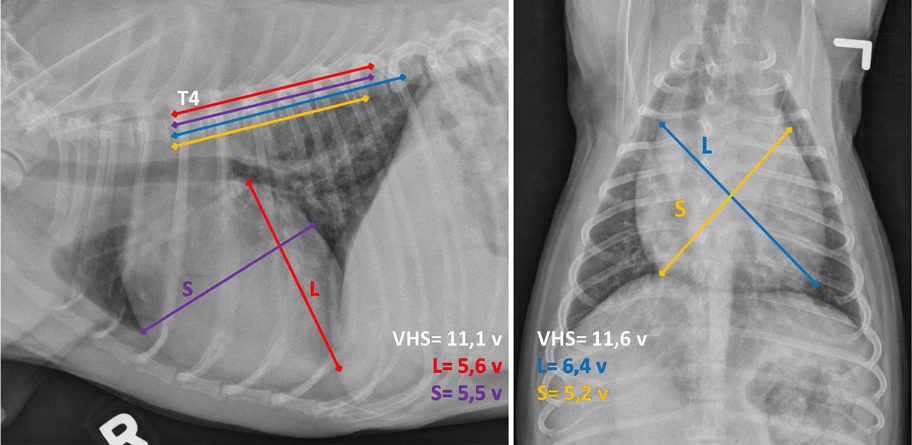

Köpeklerde Kalp Silüetinin Objektif Değerlendirilmesi

Toraks radyogramlarında küresel biçimdeki kalp görüntüsü, bütün olarak kardiyak ve perikardial oluşumlardan ibaret olduğu için değerlendirilen, kalbin kendisi değil, kalp silüetidir. Kalp silüetinin boyutunun ölçülerek...